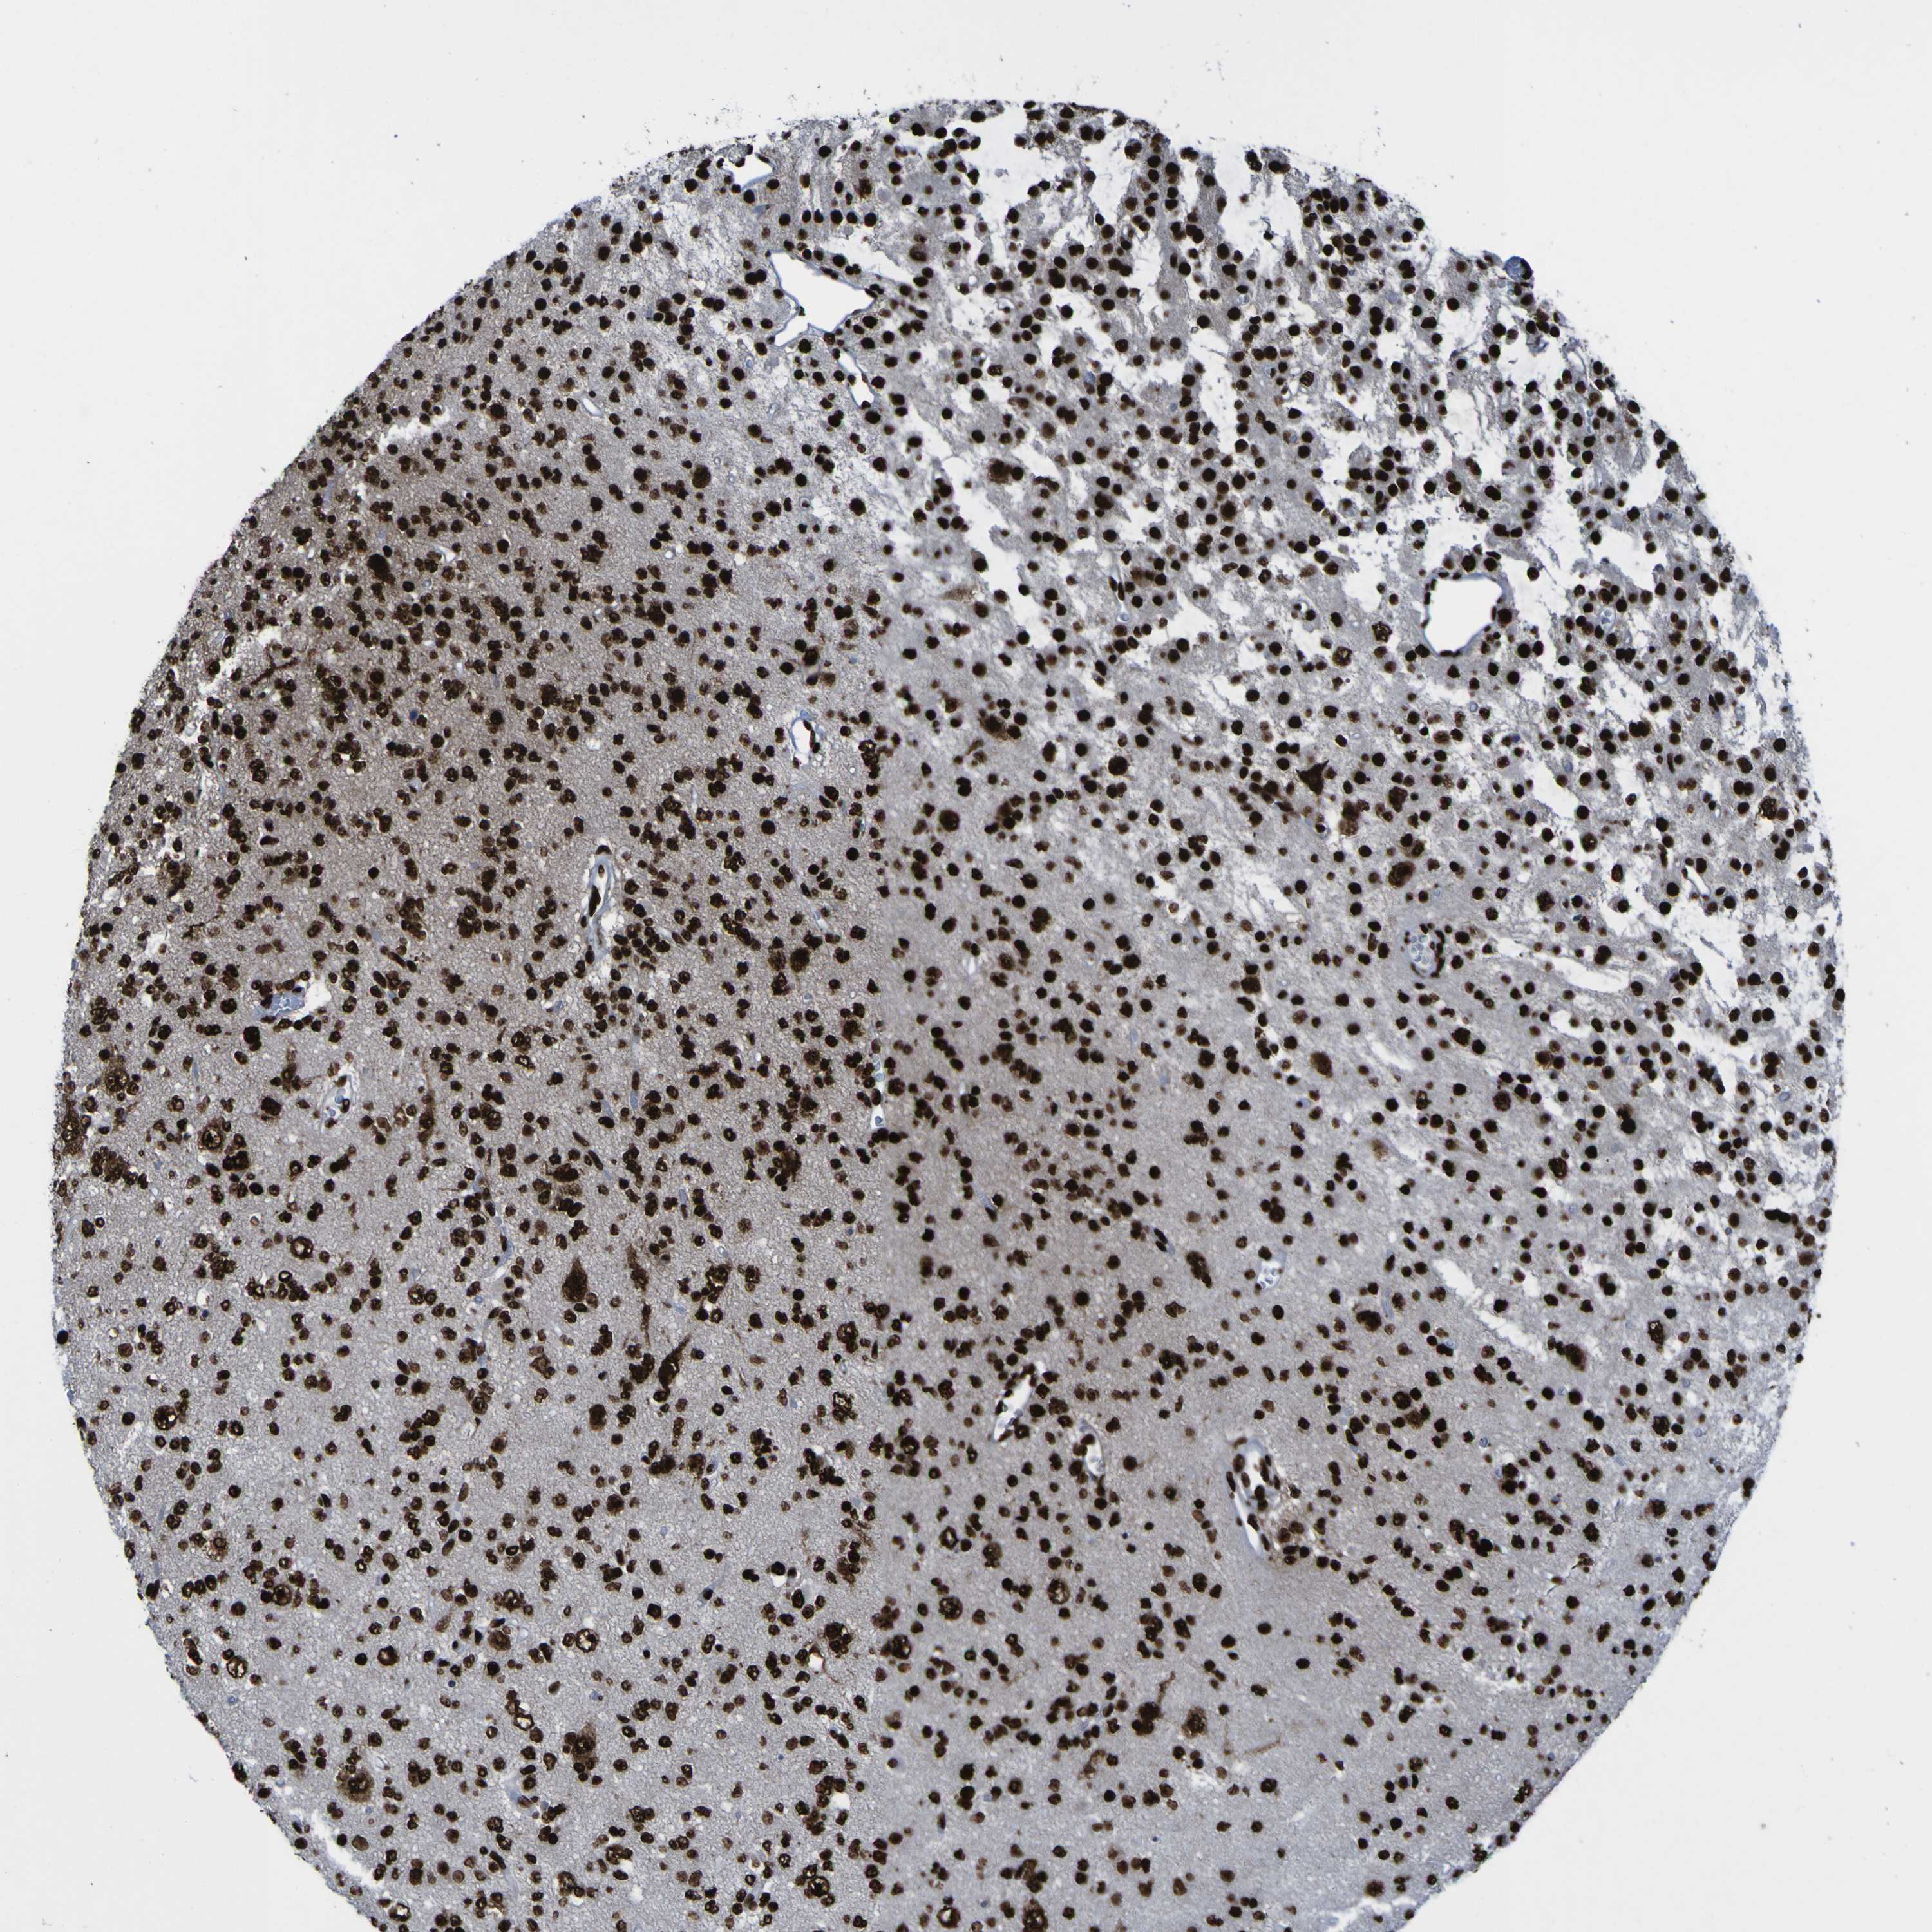

GLIOMA - Protein expressioni

A mouse-over function shows sample information and annotation data. Click on an image to view it in a full screen mode. Samples can be filtered based on level of antibody staining by selecting one or several of the following categories: high, medium, low and not detected. The assay and annotation is described here.

Note that samples used for immunohistochemistry by the Human Protein Atlas do not correspond to samples in the TCGA dataset.

Antibody stainingi

Antibody staining in the annotated cell types in the current human tissue is reported as not detected, low, medium, or high, based on conventional immunohistochemistry profiling in selected tissues. This score is based on the combination of the staining intensity and fraction of stained cells.

Each image is clickable and will lead to virtual microscopy that enables deeper exploration of all samples and also displays staining intensity scores, fraction scores and subcellular localization as well as patient and tissue information for each sample.

Antibody HPA011384

Antibody CAB012983

Staining

High

Medium

Low

Not detected

Intensity

Strong

Moderate

Weak

Negative

Quantity

>75%

75%-25%

<25%

None

Location

Nuclear

Cytoplasmic/membranous

Cytoplasmic/membranous,nuclear

Glioma, malignant, High grade

Glioma, malignant, Low grade